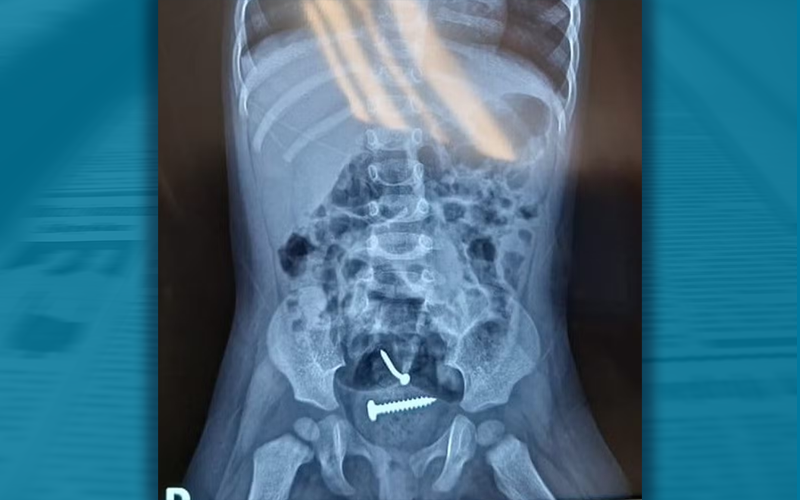

A polícia civil prendeu nesta terça-feira (19) o homem suspeito de violentar a própria filha, uma menina de 1 ano, em Pedro II, Norte do Piauí. Exames mostraram parafusos dentro do corpo da criança, o que está sendo investigado pela equipe médica.

Exames mostraram parafuso no corpo da menina.

A menina de 1 ano e a mãe foram encontradas desacordadas, na segunda-feira (18), em um terreno na zona rural e encaminhadas para o hospital. Após exames, médicos encontraram parafusos dentro do corpo da criança.

De acordo com a Polícia Militar, o caso foi denunciado pelo hospital para onde as vítimas foram levadas. Ao chegar à unidade, um raio-X apontou a presença de objetos estranhos no corpo da criança, que também tinha lesões nas partes íntimas.